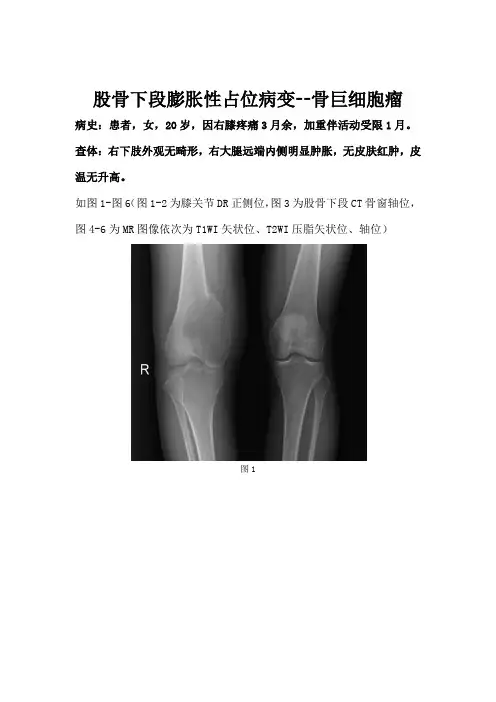

股骨下段膨胀性占位病变--骨巨细胞瘤病史:患者,女,20岁,因右膝疼痛3月余,加重伴活动受限1月。

查体:右下肢外观无畸形,右大腿远端内侧明显肿胀,无皮肤红肿,皮温无升高。

如图1-图6(图1-2为膝关节DR正侧位,图3为股骨下段CT骨窗轴位,图4-6为MR图像依次为T1WI矢状位、T2WI压脂矢状位、轴位)图1图2图3图4图5图6 基础解剖影像:图7图8图9图7-8所示为正常右侧膝关节DR正侧位图像,黄色箭头所示为股骨下段,白色箭头所示在正位片为股骨干骺端与髌骨重叠影,侧位片可以清晰看到髌骨,棕色箭头所示为胫骨上段,蓝色箭头所示为腓骨上段,所示右侧膝关节间隙未见增宽变窄,所见股骨、胫骨、腓骨、髌骨皮髓质显示清晰,周围软组织未见异常改变;图9为所示病例同层面正常股骨下段CT软组织窗轴位,黄色箭头所示为股骨,骨皮质显示为高密度影,内部髓腔为低密度影,周围脂肪间隙清晰,清楚显示周围肌肉结构。

图1图2图3图4图5图6DR正侧位(图1-2):右侧股骨下段内侧可见偏心性膨胀性骨质破坏区(蓝色箭头),未突破关节面,周围似见硬化缘,股骨下段内侧骨皮质局部变薄、中断,上缘骨膜增厚,似见Codman三角,侧位片似见条形分隔及硬化缘(棕色箭头)。